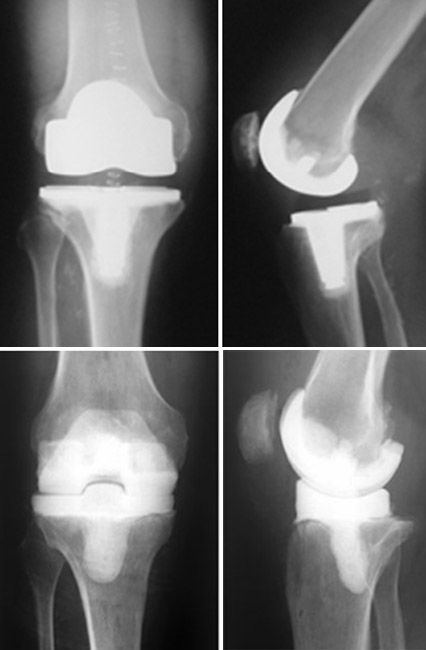

Knee replacement implants

Examples of total knee implants. Joint replacement implants are typically made of metal alloys and strong, durable plastic called polyethylene.

Photos courtesy of Stuart J. Fischer, MD, FAAOS